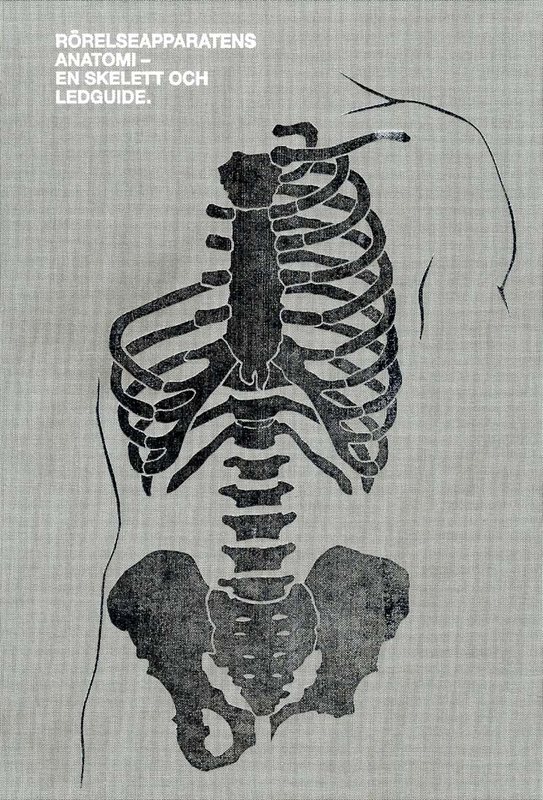

RÖRELSEAPPARATENS ANATOMI En skelett- och ledguide

258 sidor med hårdpärm. Nu med både den allmänna skelett- och ledläran samt nerver, kärl och en test-del. Boken beskriver den allmänna och speciella skelett- och ledläran med över 200 bilder i färg.

Skelettet och lederna beskrivs både enskilt och i större sammanhang med text och flera bilder. Därutöver innehåller varje kapitel intressanta ortopediska fakta om frakturtyper, ledsjukdomar och kapsulära mönster. Boken innehåller dessutom två helt nya kapitel med de större blodkärlen och nerver samt ett kapitel med de vanligast förekommande nerv och ledtester. Boken innehåller även en teoridel där den anatomiska terminologin visas genom läges- och rörelsebeskrivningar med illustrativa bilder. Precis som Rörelseapparatens anatomi en muskel- och triggerpunktsguide är den pedagogiskt upplagd och riktar sig till studenter och praktiserande inom olika kroppsterapeutiska yrken. Författare: Kristian Berg.